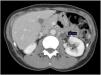

During follow-up, a possible para-aortic tumour recurrence and a lymphadenopathy suspected of malignancy were observed (Fig. 1). A PET-CT scan demonstrated a doubtful uptake in the retroperitoneal lesion (Fig. 2). In view of a possible tumour recurrence, the patient was assessed in conjunction with Internal Medicine. She had three major criteria for tuberous sclerosis (acoustic neurinoma, pulmonary lymphangioleiomyomatosis and retroperitoenal PEComa) and it was decided to start treatment with m-TOR inhibitors (sirolimus 2mg daily). Sirolimus levels are monitored every two months. After 3 months, a follow-up CT scan showed radiological improvement of the lesions with a decrease in the size of the mediastinal and retroperitoneal adenopathies described. (Fig. 3). At the present time, the patient has no signs of recurrence in control imaging tests and continues treatment with sirolimus, very well tolerated and without relevant adverse effects.